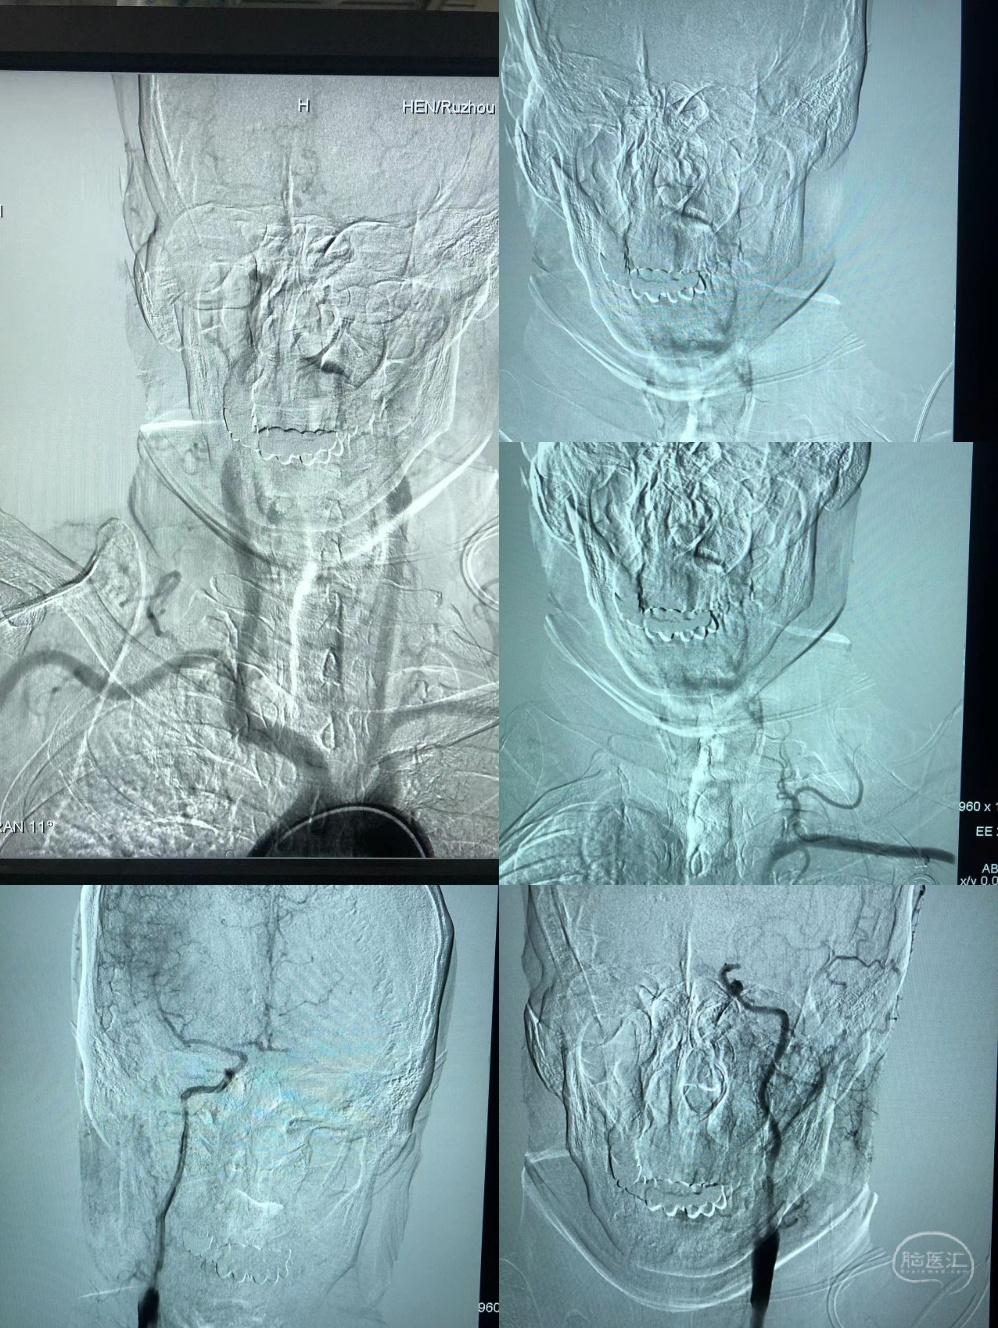

造影:左侧大脑中动脉闭塞,左侧椎动脉闭塞。

Synchro200mm微导丝配合Rebar18微导管穿越闭塞段,经Navien及微导管造影提示闭塞段位于左侧大脑中动脉中段,闭塞段很短,推测血栓负荷量极少。

送入300mmSynchro微导丝,Gateway2.5*9mm球囊扩张后,观察血流,出现弹性回缩。再次扩张后,撤出球囊,交换PLUS导管,送入Enterprise4.0*23mm支架,顺利释放,血流维持可,轻度残余狭窄。

术后造影,血流通畅,TICI分级3级。